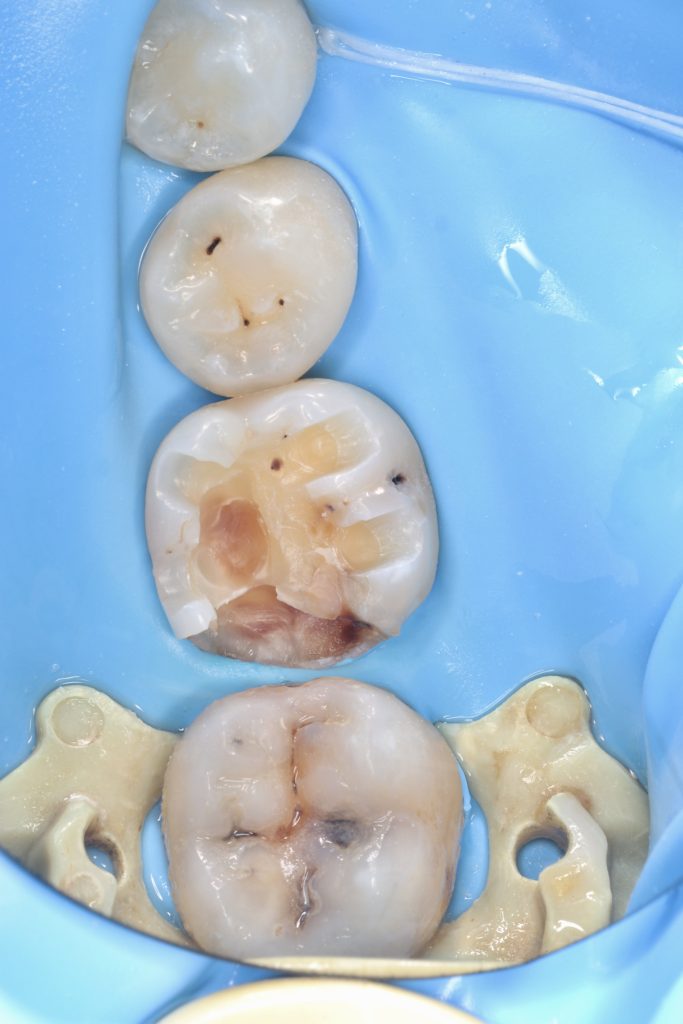

3.6 in-direct resin ceramic

3.7 direct composite

3.6 is not recommended for direct restoration due to the thickness of the cusps.